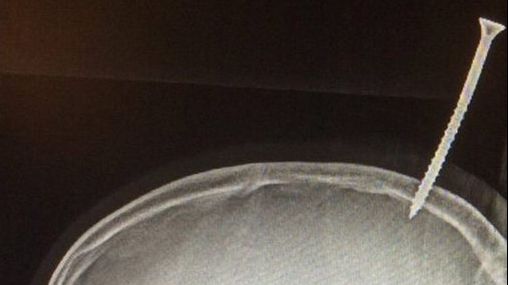

31 ian. 2018, 18:26ActualCaz medical înfricoșător: Un șurub de 15 cm a perforat creierul unui băiat de 13 ani